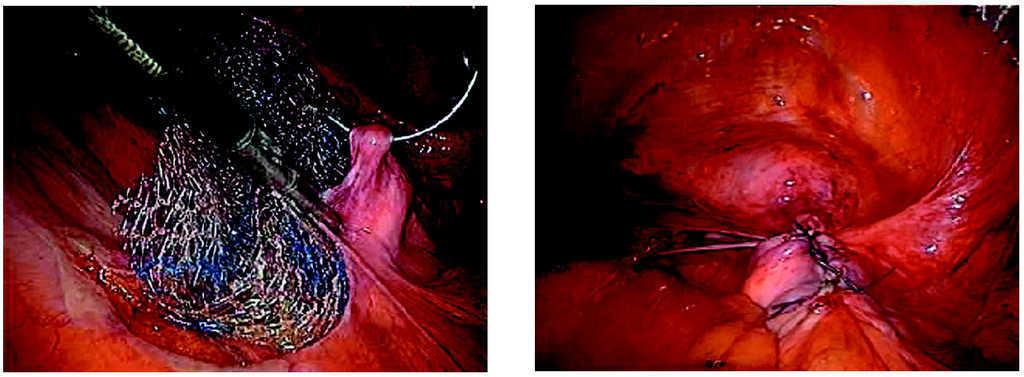

-- Paso primero. Disección laparoscópica del peritoneo presacro hasta fórnix vaginal por su vertiente derecha (fig. 4).

Figura 4.Detalle de la disección del peritoneo presacro.

-- Paso segundo. Fijación de la malla al promontorio del sacro por medio de grapas helicoidales, tipo táquer, o con puntos endoscópicos de sutura no reabsorbible (fig. 5).

Figura 5.Detalle de la fijación de la malla al promontorio.

-- Paso tercero. Peritonización con puntos sueltos (figs. 6 y 7).

Figuras 6 y 7.Detalle de la peritonización final de la malla.